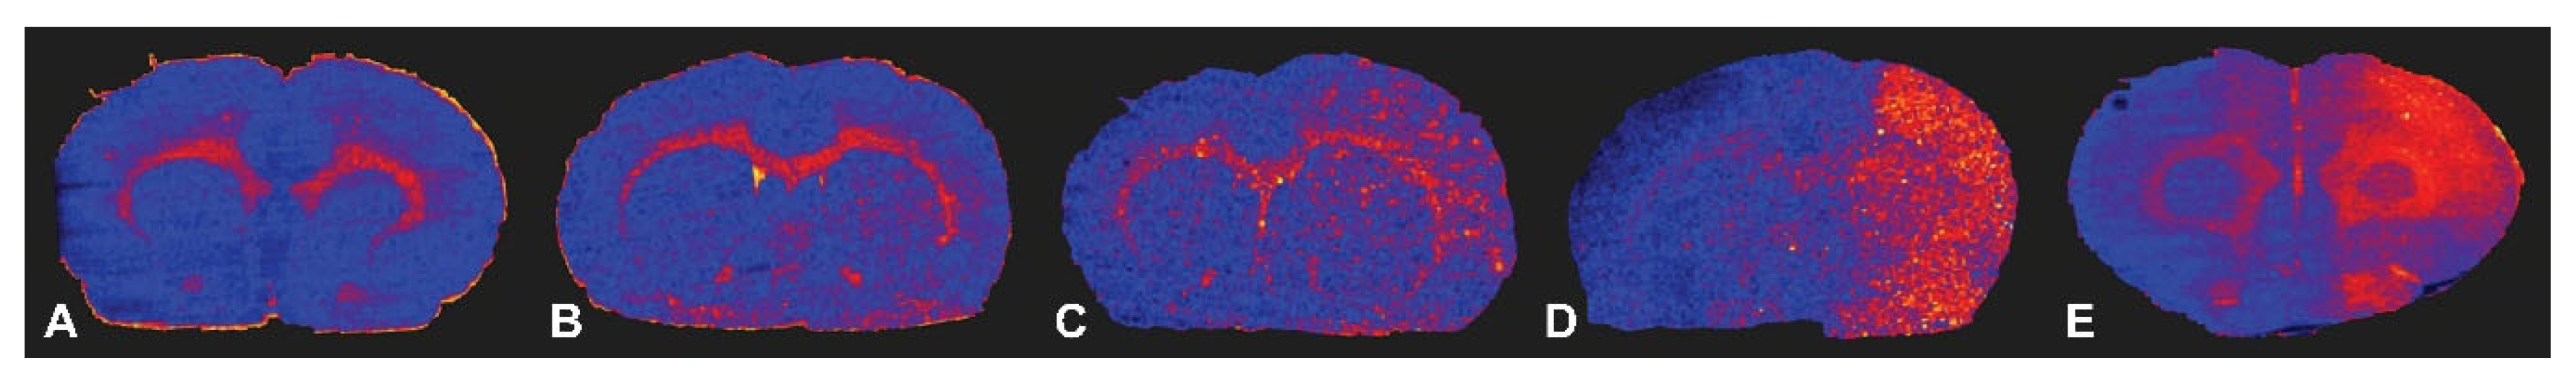

The signal intensity of TMZ was significantly higher in the ipsilateral hemisphere than in the contralateral hemisphere in all SFA emulsion groups 1 h after SFA emulsion infusion on DESI-MS images (Figure 5). Moreover, the signal intensity was lower in the butyric and valeric acid-treated groups than in the other groups. The signal intensity of the caprylic acid group was the highest among the five groups.

Figure 5. Desorption electrospray ionization-mass spectrometry (DESI-MS) images of temozolomide (TMZ) delivery to the five SFA groups at 1 h after each emulsion infusion. Minimally high signal intensity was observed in the ipsilateral hemisphere than in the contralateral hemisphere in butyric (A), valeric acid (B), and caproic acid (C) groups. The ipsilateral high signal intensity was marked in enanthic (D) and caprylic acid (E) groups.